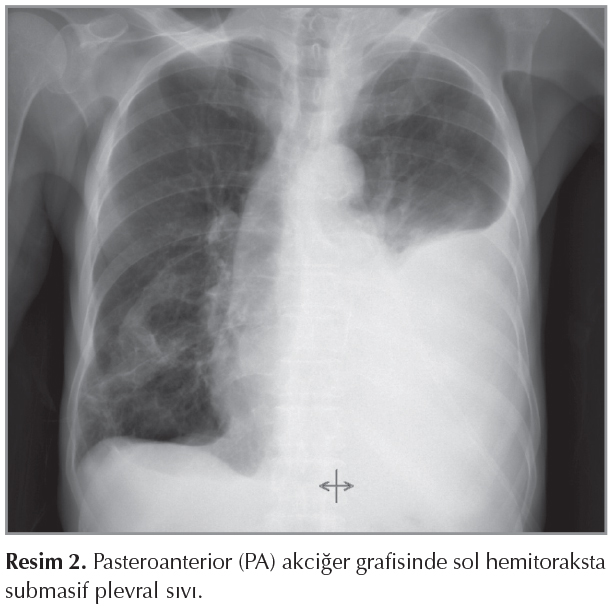

Hasta taburculuğundan ?? g?n sonra nefes darlığında artış olması ?zerine acil servise başvurdu. Muayenesinde sol akciğer bazalinde perk?syon ile matite saptandı, aynı alanlarda solunum sesi alınamadı. Rutin kan tetkiklerinde C-reaktif protein (CRP) 27.2 mg/L, diğer değerleri normal idi. Acil Serviste ?ekilen PA akciğer grafisinde sol hemitoraksta submasif plevral sıvı izlendi (Resim 2). G?ğ?s cerrahisi tarafından değerlendirilen hastaya sol hemitoraks posterolateralden diagnostik torasentez yapıldı ve 1200 cc s?t renginde plevral sıvı drene edildi (Resim 3). Plevra sıvısı trigliserid (TG) d?zeyi 1372 mg/dL olarak saptandı ve şilotoraks tanısı kondu. Ardından pleurokan kateter takıldı. Plevral sıvısının hem mikrobiyolojik incelemesinde ?reme olmadı hem de sitolojik değerlendirmesinde malignite bulgusu saptanmadı. Şilotoraks tanısı ile hasta servise alındı. Hastanın oral alımı stoplanarak total parenteral n?trisyon (TPN) başlandı. Hasta g?nl?k ?ekilen PA akciğer grafisiyle g?ğ?s cerrahisi ile birlikte takip edildi.

Resim 2

Olgumuzda ikinci kez acil servise nefes darlığı nedeniyle başvurduğunda sol akciğerde g?r?len tek taraflı submasif plevral sıvı mevcuttu. Diagnostik torasentez yapılan hastanın plevral sıvısının s?t rengi g?r?n?mde olması ve hastanın lenfoma tanısının bulunması şilotoraks a?ısından ş?phe oluşturmuştur ve plevral sıvıda trigliserid (TG) d?zeyi de rutin torasentez tetkiklerine ek olarak g?nderilmiştir.